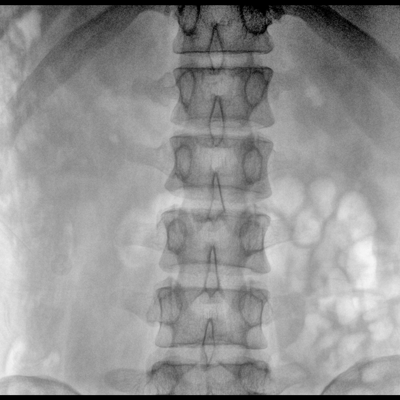

在球管和平板探測器兩端,分別加裝了激光定位系統,滿足不同擺位無射線下的定位需求,降低醫患輻射劑量的同時,提高臨床工作效率。

具備束光器預覽功能,可以在無射線狀態下,實現曝光范圍大小的調節;大幅減少臨床反復曝光帶來的射線輻射;并自動調整圖像興趣區大小與位置,使自動模式更準確。